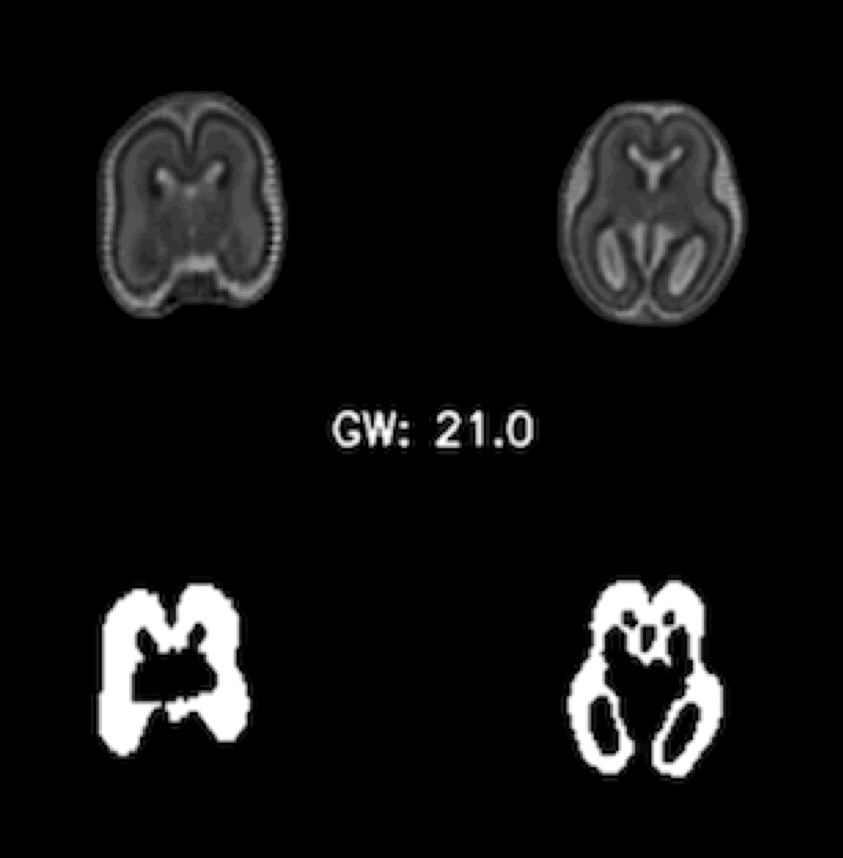

Mapping the Ganglionic Eminence in 3D: an automated tool to encode its growth trajectory in the fetal brain MRI.

The ganglionic eminence (GE) is a transient fetal brain structure crucial for neural migration, yet automatic segmentation is hindered by small size, changing morphology, and image contrast inconsistency. Tomasso proposes a deep learning–based 3D UNet, trained with augmented fetal data generated by a registration-driven approach, to segment the GE from 19 to 38 gestational weeks. This approach enables to capture and analyse the GE growth trajectories in fetal brain MRI.

Paper | Code